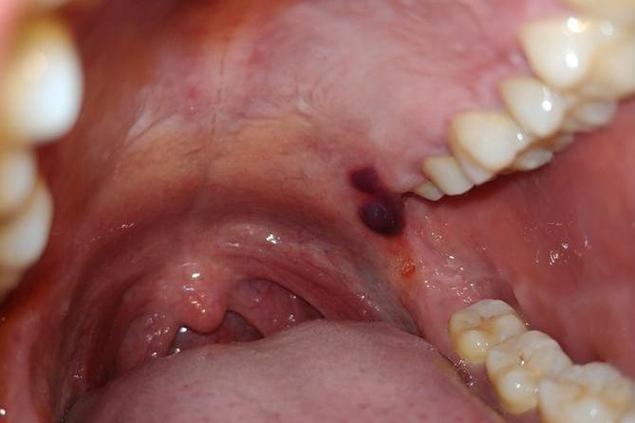

口腔里的“血泡”最常见的是两种:创伤性血疱 和 粘液囊肿(含血性),它们的形态和成因不同。

创伤性血疱

- 外观描述:

- 位置: 最常见于软腭、颊黏膜(腮帮子内侧)、唇内侧等容易被咬到的部位,舌侧缘也可能发生。

- 形态: 通常是圆形或椭圆形的隆起,边界清晰。

- 颜色: 刚形成时是鲜红色或暗红色,像一个小血球,随着时间推移(几小时到一天内),血液可能部分凝固,颜色会变成暗紫色、蓝紫色甚至深褐色。

- 大小: 大小不一,小的如米粒,大的可能像一元硬币或更大。

- 内容物: 泡内充满液体血液,摸上去柔软、有波动感(像水泡,但里面是血),如果泡壁很薄,有时能看到里面流动的血液。

- 周围黏膜: 通常周围黏膜是正常的,没有明显红肿(除非合并感染)。

- 感觉: 通常不痛或只有轻微胀痛感,除非位置特别敏感或反复摩擦刺激,有时在咬伤的瞬间会感到刺痛。